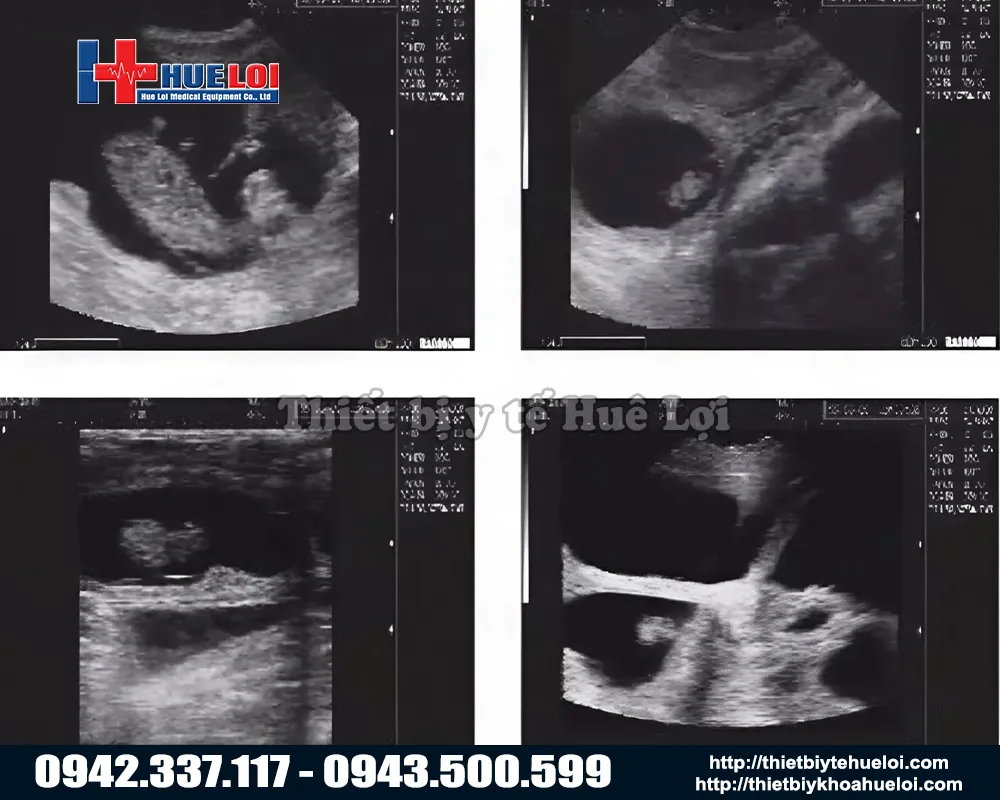

Máy siêu âm xách tay WELL.D M3V là giải pháp chẩn đoán thai và đo độ dày mỡ lưng di động hàng đầu, được thiết kế chuyên biệt cho ngành chăn nuôi lợn hiện đại. Máy sử dụng công nghệ sóng âm tần số cao, thiết bị cho phép tầm soát thai sản và kiểm tra nội tạng một cách an toàn, chính xác và hoàn toàn không xâm lấn. Với kết cấu bền bỉ, nhỏ gọn cùng pin sạc tiện dụng, M3V đóng vai trò như một 'phòng khám di động', hỗ trợ bác sĩ thú y đưa ra kết quả tức thì ngay tại chuồng trại mà không cần di chuyển vật nuôi.

2. Công Nghệ Hình Ảnh "Mimage" Vượt Trội

Dù là máy cầm tay nhỏ gọn, M3V được trang bị nền tảng siêu âm y tế với công nghệ hình ảnh "Mimage", mang lại chất lượng hình ảnh chẩn đoán sắc nét và rõ ràng đáng kinh ngạc. Với màn hình LCD 7 inch lớn so với các dòng cầm tay (thường chỉ 5-5.5 inch). Tỷ lệ 16:9 giúp việc quan sát các chi tiết nhỏ trở nên dễ dàng hơn bao giờ hết.